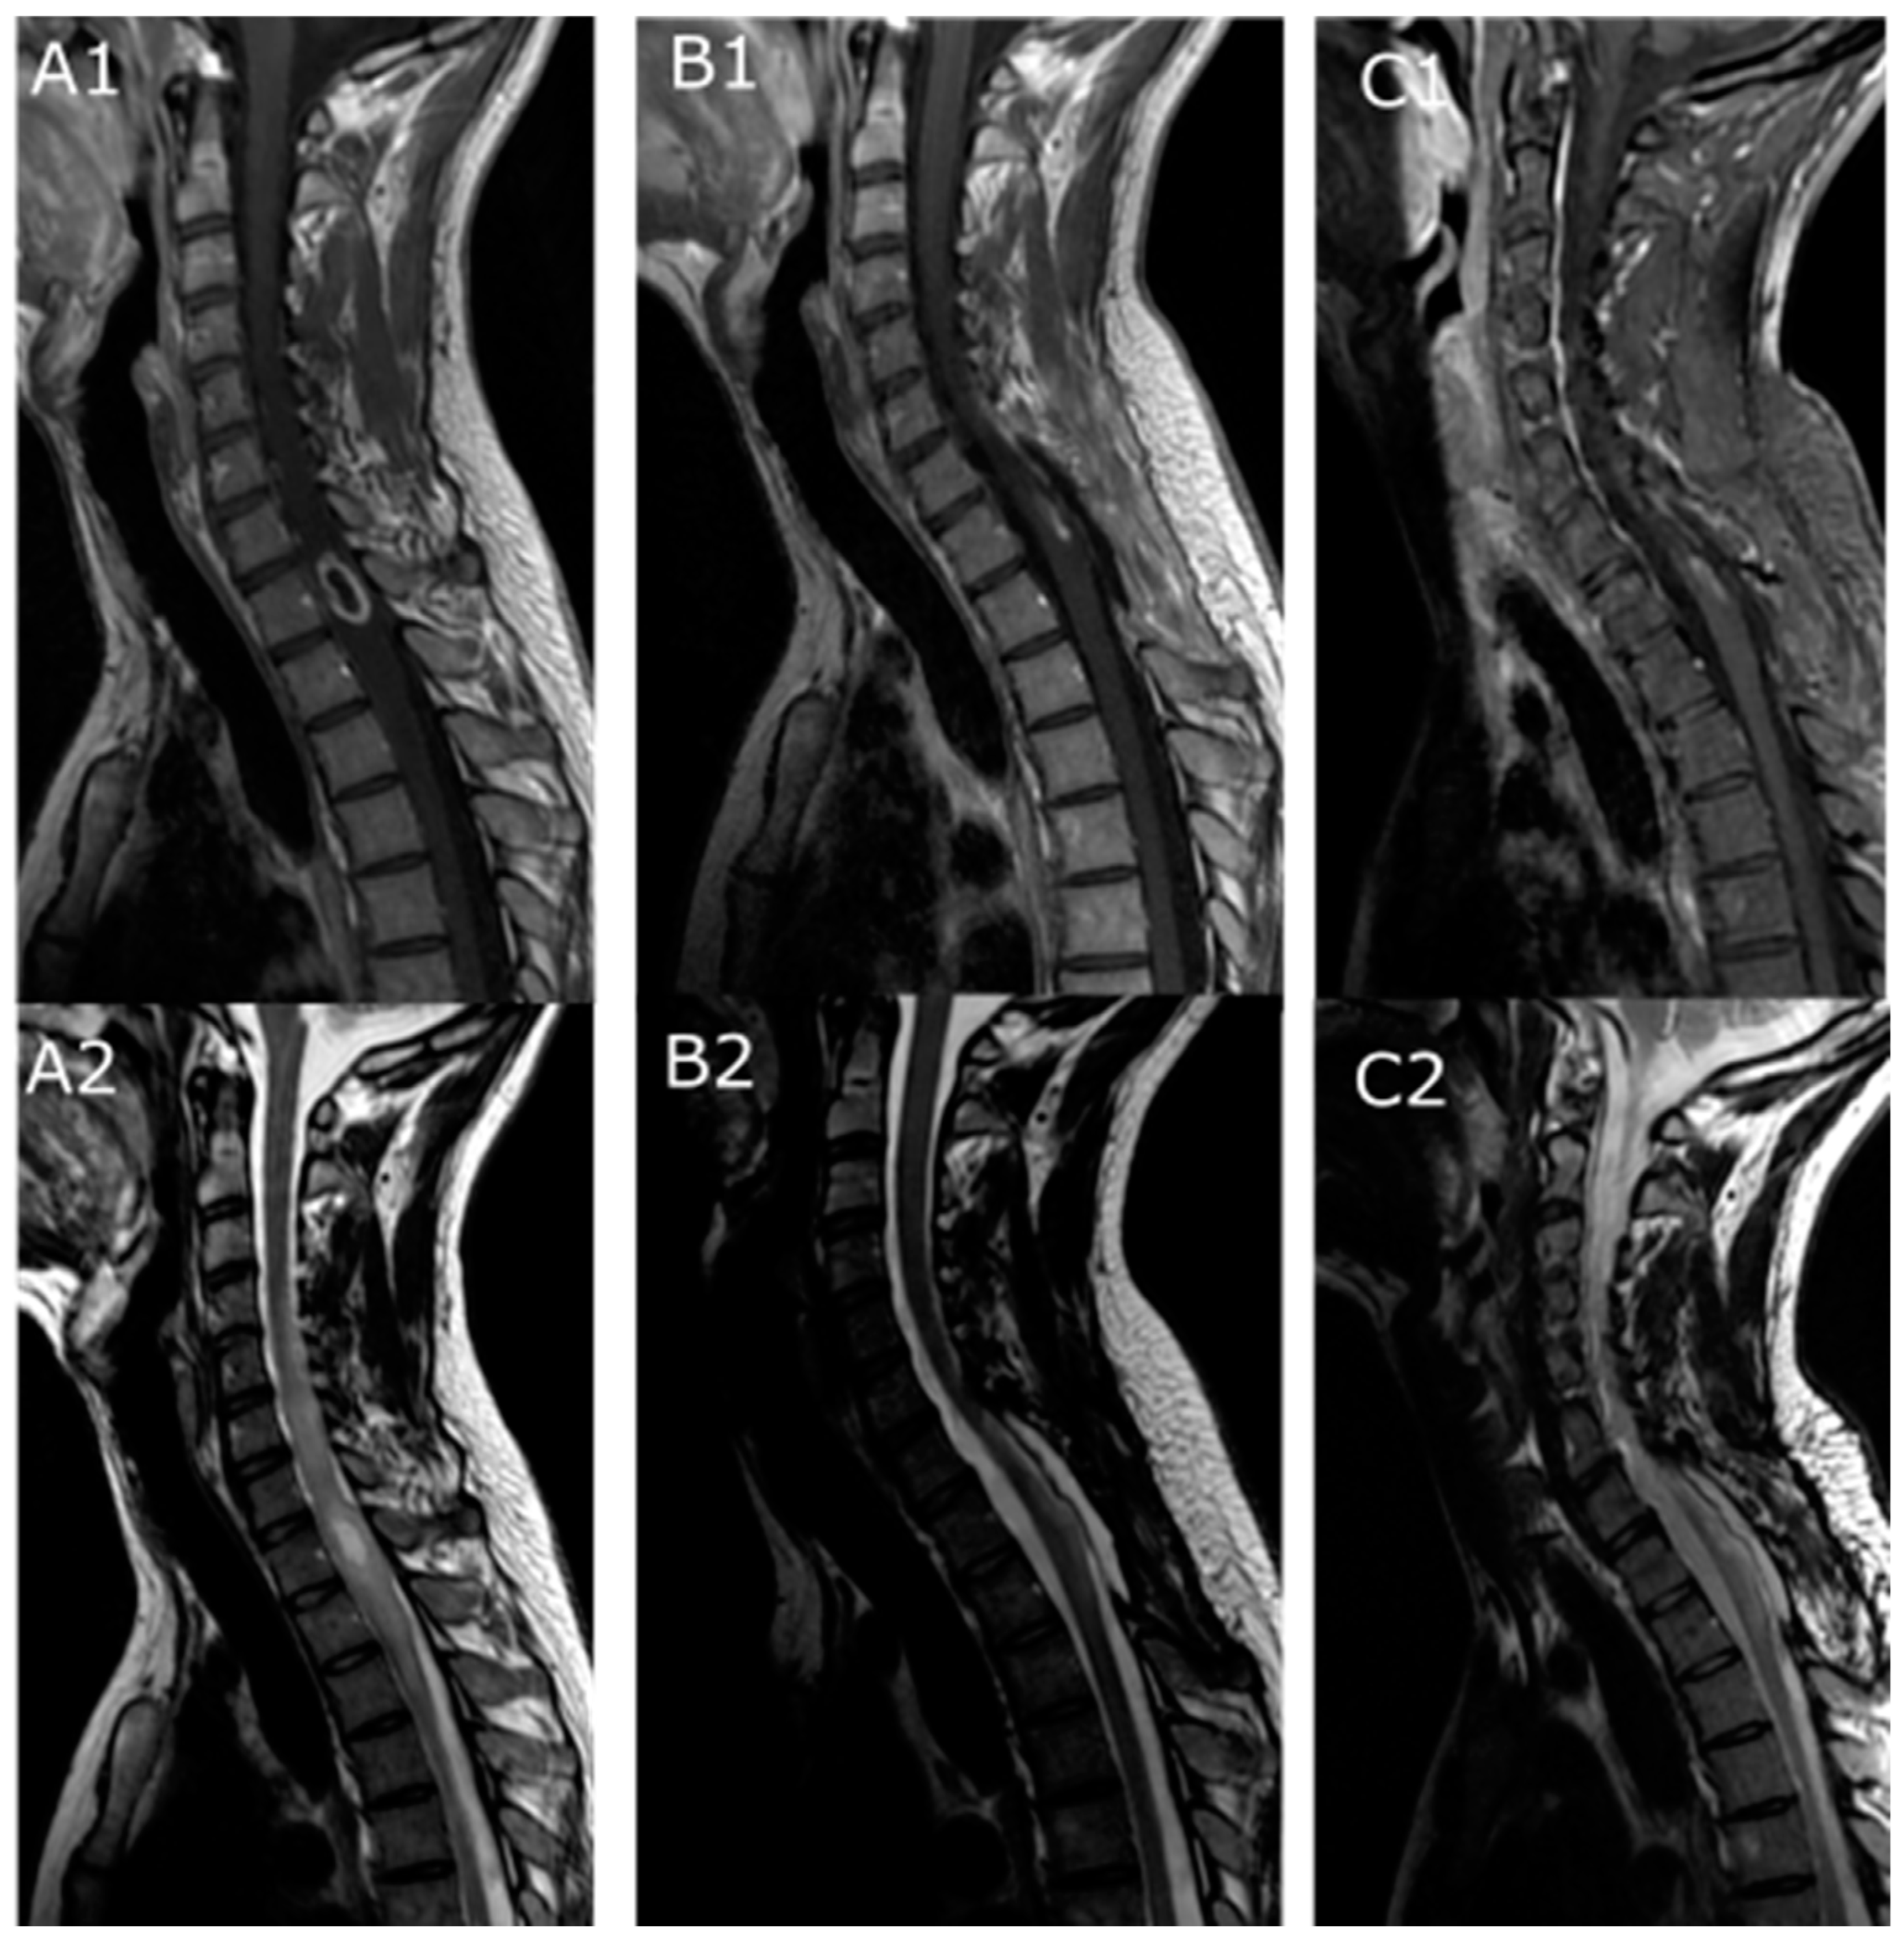

| T1-weighted sequence signal (%) | Hypo | 11/23(47.8%) |

| Iso | 10/23 (43.5%) | |

| Hyper | 2/23 (8.7%) | |

| T2-weighted sequence signal (%) | Hypo | 2/24 (8.3%) |

| Iso | 0 | |

| Hyper | 22/24 (91.7%) | |

| Gadolinium enhancement | 26 (86.7%) | |

| Peritumoral cyst | 18/29 (62%) | |

| Peritumoral hemorrhage | 9/28 (32.1%) | |